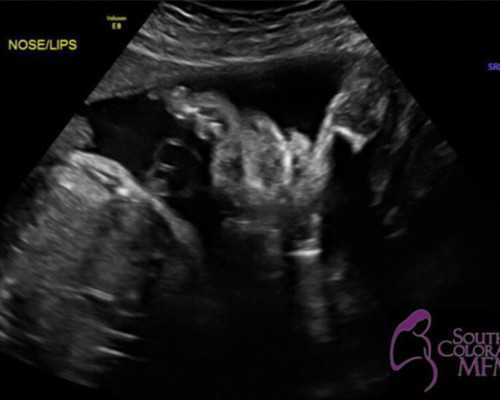

试管婴儿手术中任意一个阶段都非常的重要,促排卵也是非常重要的,7种促排方案针对不同的人群,如黄体期方案针对高龄以及多囊卵巢综合征等患者,而促排药物与促排针的使用对于人体都会有一定的伤害,而自然周期方案优势来说则完全可以避免这些情况。

促排的开始也就代表着试管婴儿手术已经提上了日程,与常见短方案、长方案以及微刺激方案等人工周期不同,自然周期对女性身体并没有伤害,自然周期优势非常的独特,但并不是说适合所有的人,促排方案是医生根据患者身体情况,不孕不育原因而助孕针对性促排卵方案。